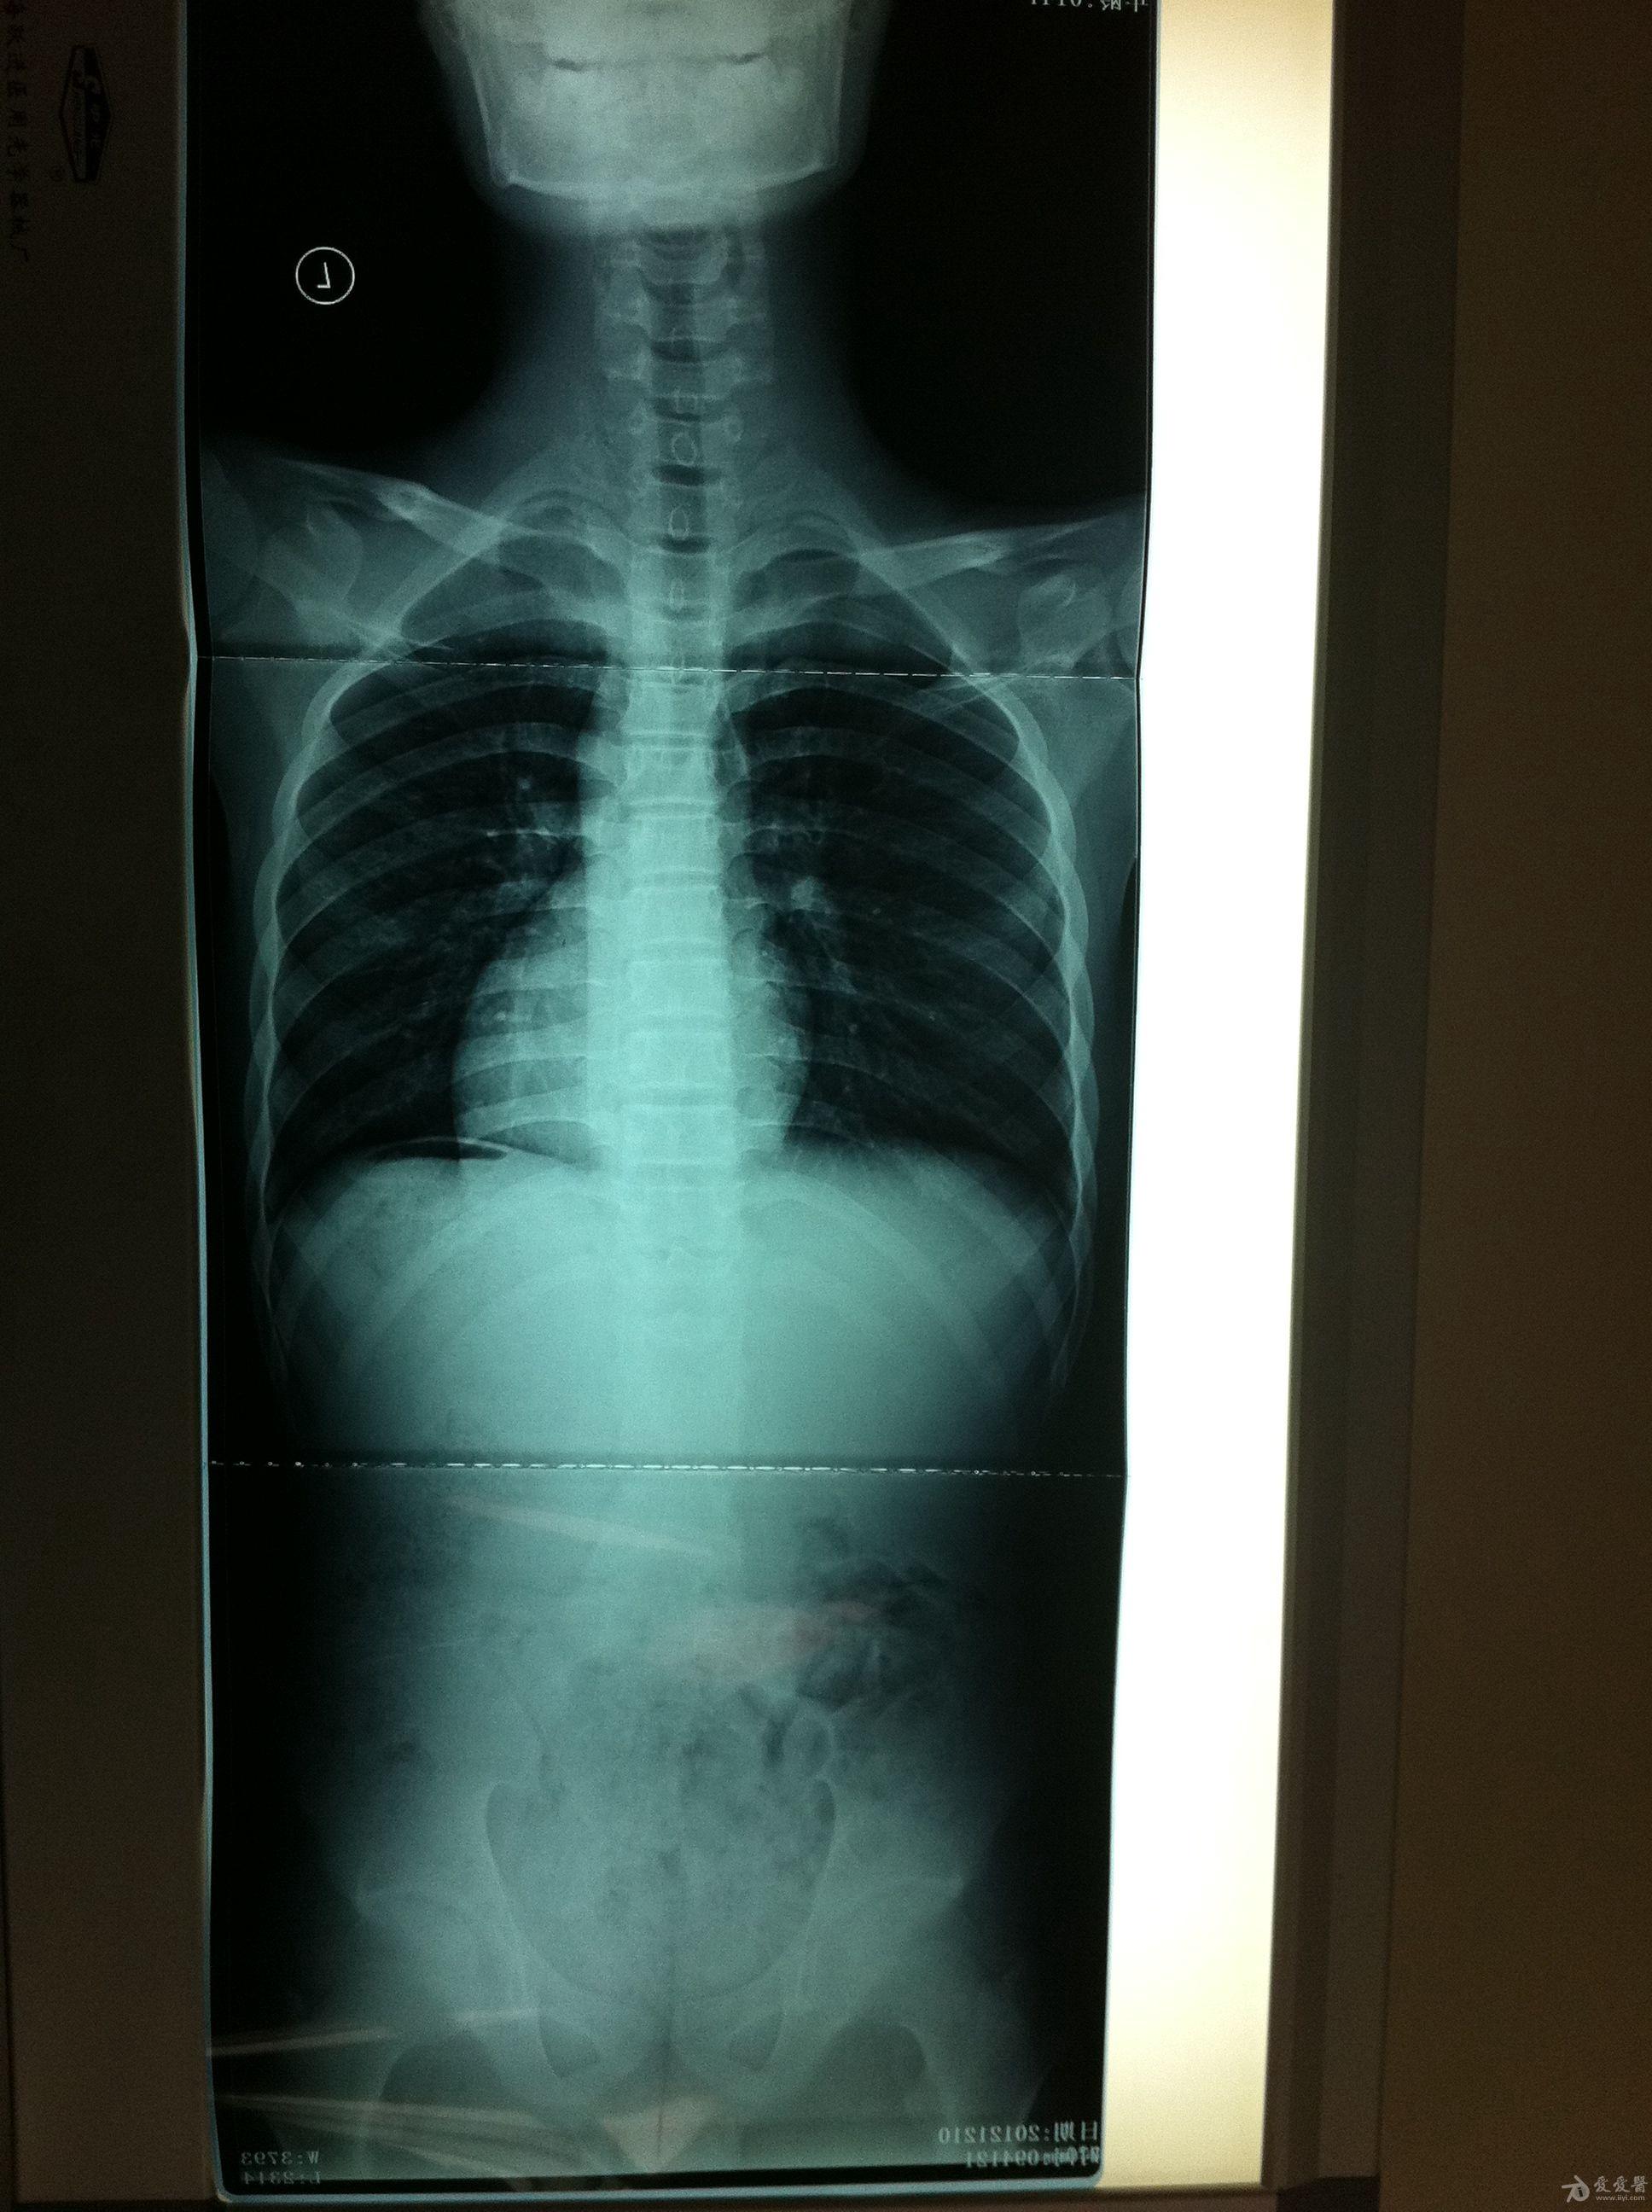

脊柱全长x光片显示胸腰段cobb角25°,身体有明显的倾斜趋势,剃刀背

剃刀背压没了右肺